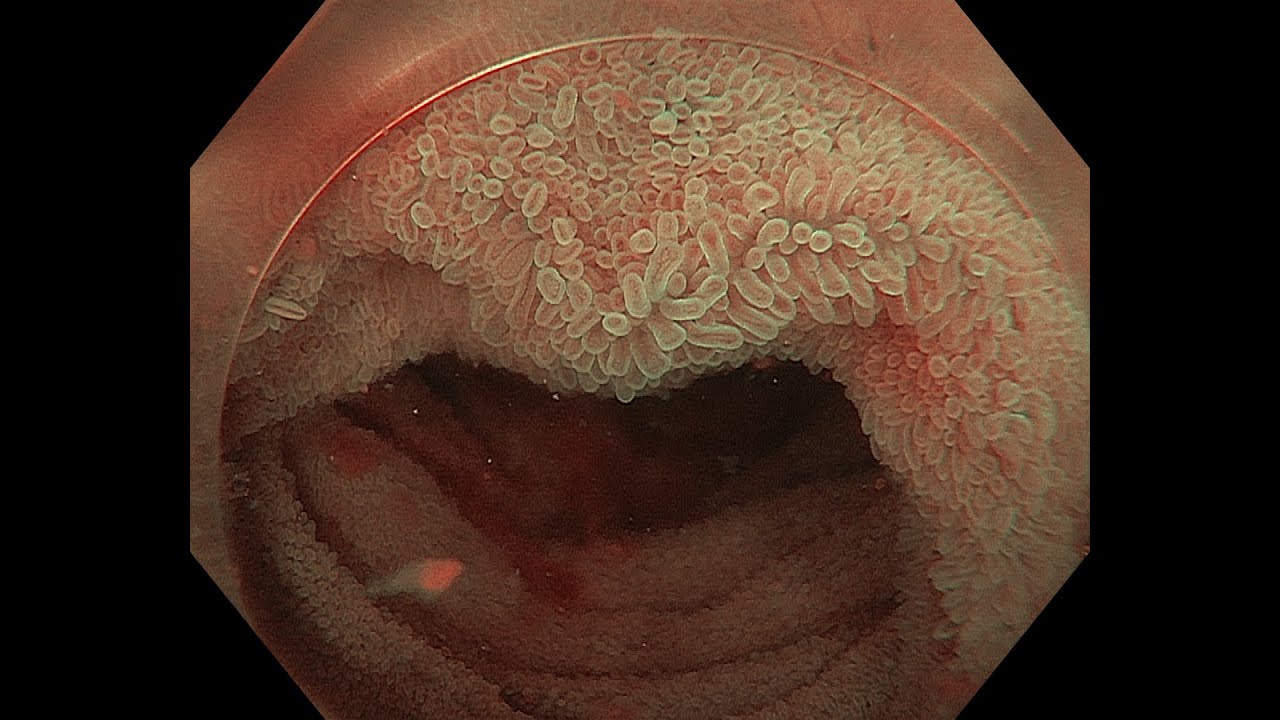

Villous Mucosa Of The Terminal Ileum Carcinoid Syndrome Animation Reference Magnification

A Case Of Gastric Adenocarcinoma Presented With Villous Or Ridge Download Scientific Diagram

Small Intestine Endoscopic View Of The Normal Interior Of A Person S Ileum The Small Intestine The Healthy Intestinal Lin Digestion Microbiome Hot Dog Buns